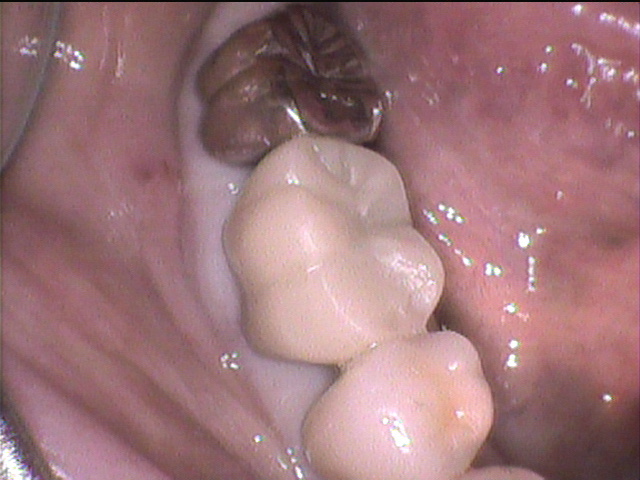

治療前写真

- 「右下の奥歯が痛くて噛めない!」

「噛める様にして欲しい!」

と言って来院されました。